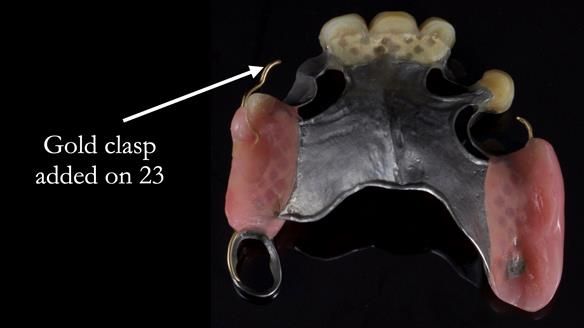

This edition features the case of Edgar, who sought help for a poorly fitting, acrylic-based partial denture that rocked, affected his speech, and caused discomfort. After considering various treatment options, including dental implants, Edgar opted for a metal-based removable partial denture, designed by myself with input from my technician, Rowan Garstang.

Treatment Process: I provided the clinical work while Rowan Garstang delivered the technical aspects. The treatment required fifteen visits to fit and review Edgar.